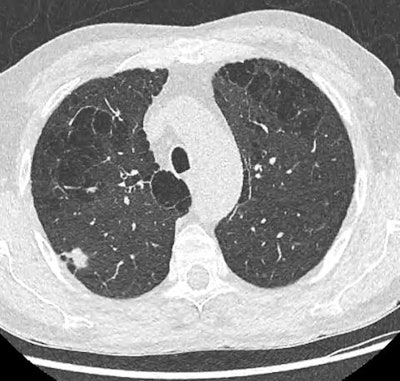

Low-dose injection-free thoracic CT scan of a 68-year-old man that was performed as part of the screening program (Prevalung study). After the workup, the patient was operated on, revealing a 14 mm adenocarcinoma classified pT1bN0M0. He is now under simple surveillance. Courtesy of Dr. Caroline Caramella and SFR and SIT.Population-based lung cancer screening also raises important organizational issues: How should at-risk subjects be recruited? How can the subjects' adherence to the screening program be ensured? What care pathway should be put in place? How can inequalities in access to screening be reduced? How should the medico-economic impact of screening be evaluated?